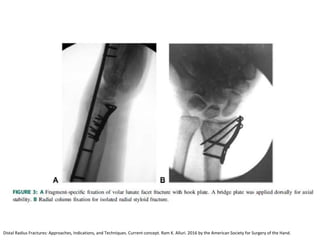

Reducción abierta + Fijación Interna

Distal Radius Fractures: Approaches, Indications, and Techniques. Current concept. Ram K. Alluri. 2016 by the American Society for Surgery of the Hand.

Tecnica artroscòpica

Estabilización de fragmento

• Estiloides

piedra angular .

• Borde volar del

radio

• C dorsal y

palmares de la

carilla lunar del

• La cavidad

Sigmoidea